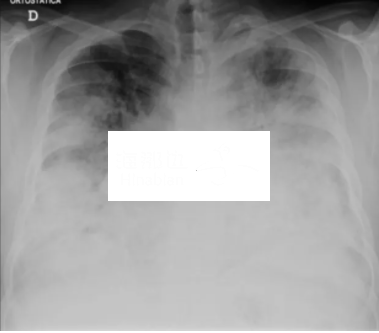

这种新型肺炎名为军团病(Legionnaires),也称退伍军人病,或军团热,是一种相当普遍并且很严重的肺炎。

军团病是由军团菌引发的非典型肺炎,致死率很高。夏末秋初是该病高发季节。男性发病多于女性,孕妇、老年、吸烟者、免疫功能低下者为高发人群。

军团病症状包括咳嗽、呼吸困难、发热、肌肉疼痛、头痛。有时亦会发生恶心、呕吐、腹泻。军团病的症状通常在暴露后2到10天产生。

这些症状和新冠感染的症状很相似,军团病一旦感染,几乎是必须入院治疗,并服用抗生素,否则可能有生命危险。

目前军团病的死亡风险比新冠要高得多,在未经治疗的免疫受损病人中可高达40%-80%。通过适当病例治疗以及视临床症状和体征的严重程度,可使死亡率降至5%-30%。总体而言,死亡率往往处于5%-10%之间,但传播率较低。